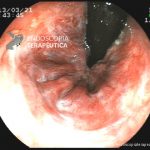

- Doença de Crohn em remissão – cicatriz